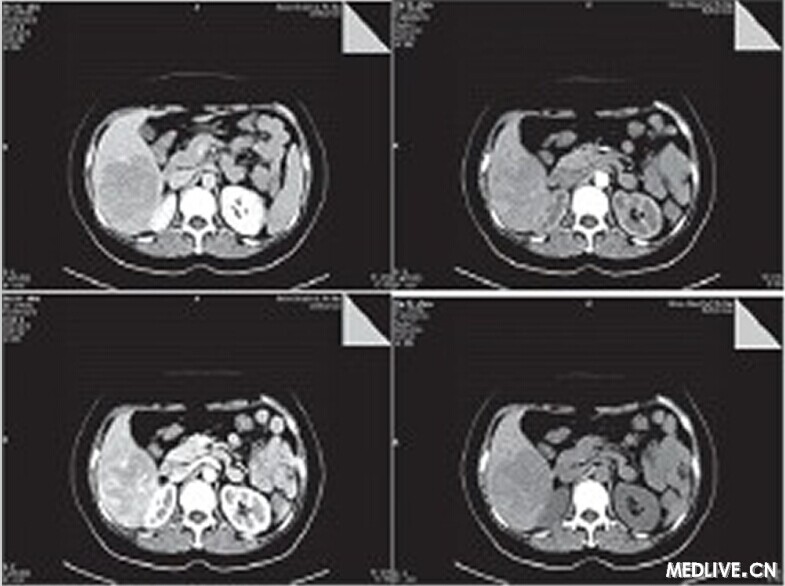

【PHILIPS每日一例】【誤診分析】肝臟血管平滑肌脂肪瘤誤診為肝癌一例

患者,女,50歲,農民。

因右上腹疼痛1月余,外院B超診斷為肝癌入我院治療。既往無肝炎病史,無飲酒史,無遺傳病史,無高血壓糖尿病史。

體檢:神志清楚,正力體型,皮膚鞏膜無黃染;心肺聽診未見異常;腹軟,肝脾肋下未及,腹水征陰性,雙下肢無水腫。

入院后輔助檢查:甲胎蛋白正常,肝功能正常,血常規正常,便常規見膿球1~3個,HBV和HCV相關病原學檢查陰性。

CT檢